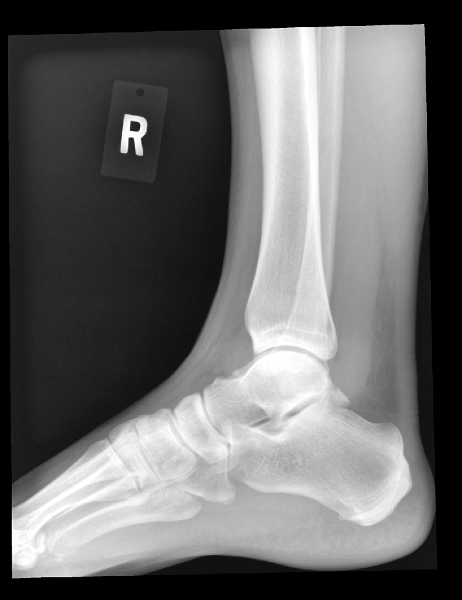

Ankle (1) Ankle (1) Ankle (2) Ankle (2) Ankle (3) Ankle (3)

Ankle (4) Ankle (4) Ankle (5)